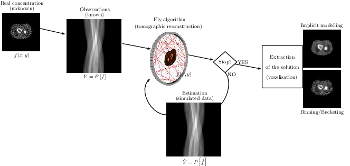

This work is based on a cooperative co-evolution algorithm called `Fly Algorithm', which is an evolutionary algorithm (EA) where individuals are called `flies'. It is a specific case of the `Parisian Approach' where the solution of an optimisation problem is a set of individuals (e.g. the whole population) instead of a single individual (the best one) as in typical EAs. The optimisation problem considered here is tomography reconstruction in positron emission tomography (PET). It estimates the concentration of a radioactive substance (called a radiotracer) within the body. Tomography, in this context, is considered as a difficult ill-posed inverse problem. The Fly Algorithm aims at optimising the position of 3-D points that mimic the radiotracer. At the end of the optimisation process, the fly population is extracted as it corresponds to an estimate of the radioactive concentration. During the optimisation loop a lot of data is generated by the algorithm, such as image metrics, duration, and internal states. This data is recorded in a log file that can be post-processed and visualised. We propose using information visualisation and user interaction techniques to explore the algorithm's internal data. Our aim is to better understand what happens during the evolutionary loop. Using an example, we demonstrate that it is possible to interactively discover when an early termination could be triggered. It is implemented in a new stopping criterion. It is tested on two other examples on which it leads to a 60% reduction of the number of iterations without any loss of accuracy. Keywords: Fly Algorithm; Tomography reconstruction; Information visualisation; Data exploration; Artificial evolution; Parisian evolution. |

The Fly Algorithm was initially developed for 3-D robot vision applications. It consists in solving the inverse problem of shape reconstruction from projections by evolving a population of 3-D points in space (the `flies'), using an evolutionary optimisation strategy. Here, in its version dedicated to tomographic reconstruction in medical imaging, the flies are mimicking radioactive photon sources. Evolution is controlled using a fitness function based on the discrepancy of the projections simulated by the flies with the actual pattern received by the sensors. The reconstructed radioactive concentration is derived from the population of flies, i.e. a collection of points in the 3-D Euclidean space, after convergence. `Good' flies were previously binned into voxels. In this paper, we study which flies to include in the final solution and how this information can be sampled to provide more accurate datasets in a reduced computation time. We investigate the use of density fields, based on Metaballs and on Gaussian functions respectively, to obtain a realistic output. The spread of each Gaussian kernel is modulated in function of the corresponding fly fitness. The resulting volumes are compared with previous work in terms of normalised-cross correlation. In our test-cases, data fidelity increases by more than 10% when density fields are used instead of binning. Our method also provides reconstructions comparable to those obtained using well-established techniques used in medicine (filtered back- projection and ordered subset expectation-maximisation). Keywords: Fly algorithm; Evolutionary computation; tomography reconstruction; iterative algorithms; inverse problems; co-operative co-evolution |

This paper shows new resutls of our artificial evolution algorithm for Positron Emission Tomography (PET) reconstruction. This imaging technique produces datasets corresponding to the concentration of positron emitters within the patient. Fully three-dimensional (3D) tomographic reconstruction requires high computing power and leads to many challenges. Our aim is to produce high quality datasets in a time that is clinically acceptable. Our method is based on a co-evolution strategy called the “Fly algorithm”. Each fly represents a point in space and mimics a positron emitter. Each fly position is progressively optimised using evolutionary computing to closely match the data measured by the imaging system. The performance of each fly is assessed based on its positive or negative contribution to the performance of the whole population. The final population of flies approximates the radioactivity concentration. This approach has shown promising results on numerical phantom models. The size of objects and their relative concentrations can be calculated in two-dimensional (2D) space. In (3D), complex shapes can be reconstructed. In this paper, we demonstrate the ability of the algorithm to fidely reconstruct more anatomically realistic volumes. Keywords: Evolutionary computation, inverse problems, adaptive algorithm, Nuclear medicine, Positron emission tomography, Reconstruction algorithms |

We present and analyse the behaviour of specialised operators designed for cooperative coevolution strategy in the framework of 3D tomographic PET reconstruction. The basis is a simple cooperative co-evolution scheme (the “fly algorithm”), which embeds the searched solution in the whole population, letting each individual be only a part of the solution. An individual, or fly, is a 3D point that emits positrons. Using a cooperative co-evolution scheme to optimize the position of positrons, the population of flies evolves so that the data estimated from flies matches measured data. The final population approximates the radioactivity concentration. In this paper, three operators are proposed, threshold selection, mitosis and dual mutation, and their impact on the algorithm efficiency is experimentally analysed on a controlled test-case. Their extension to other cooperative co-evolution schemes is discussed. |

This paper presents an evolutionary approach for image reconstruction in positron emission tomography (PET). Our reconstruction method is based on a cooperative coevolution strategy (also called Parisian evolution): the “fly algorithm”. Each fly is a 3D point that mimics a positron emitter. The flies' position is progressively optimised using evolutionary computing to closely match the data measured by the imaging system. The performance of each fly is assessed using a “marginal evaluation” based on the positive or negative contribution of this fly to the performance of the population. Using this property, we propose a “thresholded-selection” method to replace the classical tournament method. A mitosis operator is also proposed. It is triggered to automatically increase the population size when the number of flies with negative fitness becomes too low. |

This paper presents a method to take advantage of artificial evolution in positron emission tomography reconstruction. This imaging technique produces datasets that correspond to the concentration of positron emitters through the patient. Fully 3D tomographic reconstruction requires high computing power and leads to many challenges. Our aim is to reduce the computing cost and produce datasets while retaining the required quality. Our method is based on a coevolution strategy (also called Parisian evolution) named “Fly algorithm”. Each fly represents a point of the space and acts as a positron emitter. The final population of flies corresponds to the reconstructed data. Using “marginal evaluation”, the fly's fitness is the positive or negative contribution of this fly to the performance of the population. This is also used to skip the relatively costly step of selection and simplify the evolutionary algorithm. |